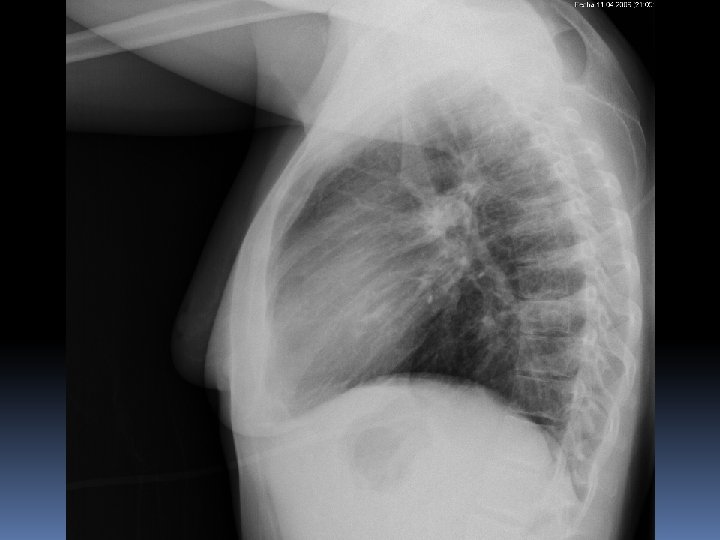

5 años mas tarde……….

2008 2013